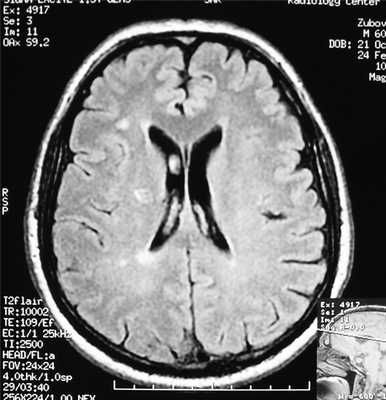

Как видно из табл. 5, в изученных случаях имелись только очаги глиоза, единичные или множественные (последние отражены на рисунке). Рисунок 1. Множественные очаги глиоза в белом веществе головного мозга на МР-томограмме пациента З., 47 лет. Напомним, что глиоз - это разрастание астроцитарной нейроглии с гиперпродукцией глиальных волокон, представляющее собой процесс ее заместительной гиперплазии в ответ на гибель нервных клеток. Этот процесс может развиваться при разных по генезу хронически протекающих очаговых или диффузных поражениях нервной системы.

Таким образом, ПЭ характеризуется рядом клинических особенностей: при умеренно выраженном цефалгическом синдроме определяются выраженная церебрастения и рассеянная неврологическая симптоматика. При этой симптоматике на МРТ головного мозга выявляются единичные и множественные очаги глиоза в белом веществе головного мозга.